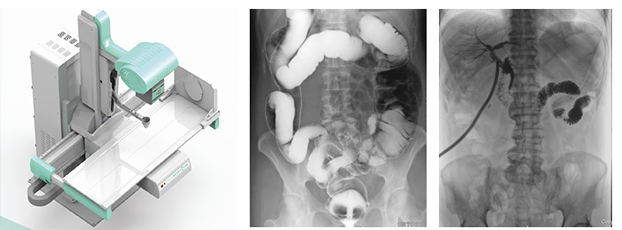

一、新一代動態平板探測器,一機多用實現動靜態采集

只需一塊動態平板探測器,即可高效輕松實現攝影、透視和造影功能,幾乎可以滿足醫院全科室的臨床檢查需求。

大尺寸動態平板技術,覆蓋檢查面積范圍廣,輕松實現胃十二指腸等大面積造影,無需移動即可觀看整個動態過程,避免噪點對圖像的影響。

3)高幀速

最高幀速可達30幀/秒,獲得與靜態采集相媲美的高清流暢影像;

采用先進的脈沖透視技術,呈現更優圖像空間分辨率、低對比度分辨率、灰階范圍,為精準診斷提供可靠依據。

4)透視+高清點片

在可視過程或回放過程中,如發現疑似病灶,可進行毫秒級高清點片,隨時抓取單幀圖像,精準捕抓病灶,便于醫生進一步診斷分析,減少誤診,并有助于快速編制報告。